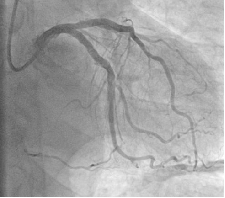

Baseline angiography showed 80% stenosis and calcification of the mid-left circumflex branch (LCX) (Fig. 1-2)